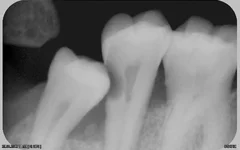

Уважаемые специалисты, подскажите, пожалуйста, если треснул корень зуба (четвёрка вверху), однозначно удалять? В зубе стоял штифт лет 5, теперь он отломался, остался только корень